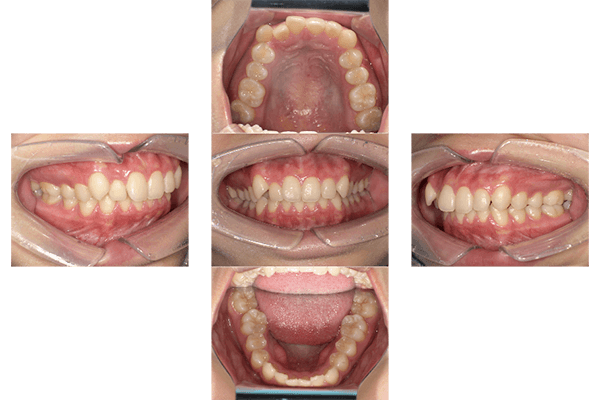

| 主訴 | 奥歯に痛みがある、前歯で噛みきれない、歯並びを治したい |

|---|---|

| 診断 | 開咬(オープンバイト) |

| 治療期間 | 2年 |

| 治療費用 | ¥792,000(税込) |

| リスクと副作用 |

|

| 院長コメント | 他の医院で矯正は難しいと言われたとのことです。奥歯ばかりが当たって歯が欠けることもあり、何とかしたいとのご希望で当院来院されました。 顎間ゴム(上あごと下あごにまたがるゴム)をかけて上の歯を奥に移動させました。「マウスピースを装着しながら接客をしたがしゃべりにくいということは無く、マスクを外しても気づかれなかった」と驚いておられました。仕上がりに大変満足され「矯正をしてよかった」とのお言葉をいただきました。治療初めの歯を動かす際は少し痛かったそうですが、その後は特に痛みを感じなかったとのことです。 |